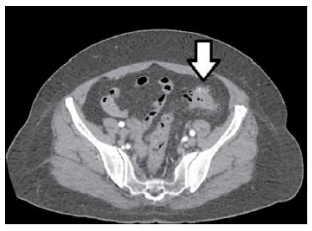

Paciente do sexo feminino, 45 anos, deu entrada no prontosocorro com queixa de dor abdominal baixa de início há 6 horas no hipogastro, com pouca resposta ao uso de analgésico em casa. Ao exame, apresentou-se estável hemodinamicamente, afebril, com dor à palpação no hipogastro e fossa ilíaca E, sem sinais de peritonite, sem massas palpáveis no abdômen. Realizada tomografia computadorizada, que produziu a imagem a seguir.

Com base nos dados apresentados, o diagnóstico para o caso em tela é: